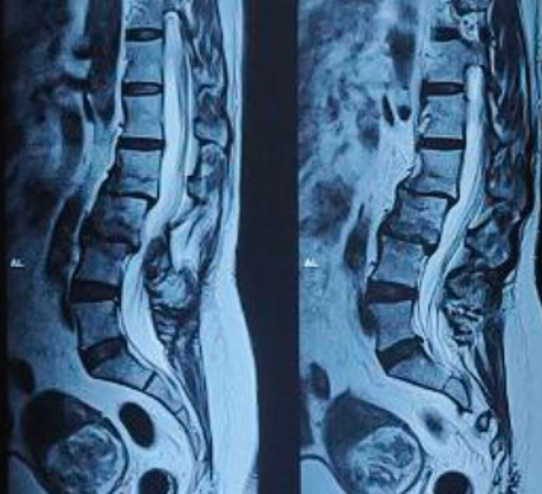

After Surgery Results

Spinal fusion is a surgical procedure that permanently joins two or more bones of the spine so they heal into one solid bone. This eliminates painful movement between them and stabilizes the spine.

The surgeon removes the damaged disc or diseased bone, places a cage or bone graft between the vertebrae, and secures it with screws and rods. Over months, the bones heal together naturally. The surgical approach (front, back, or side) depends on the patient's specific condition and body type.